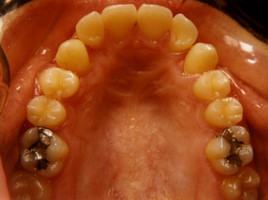

Προ Θεραπείας